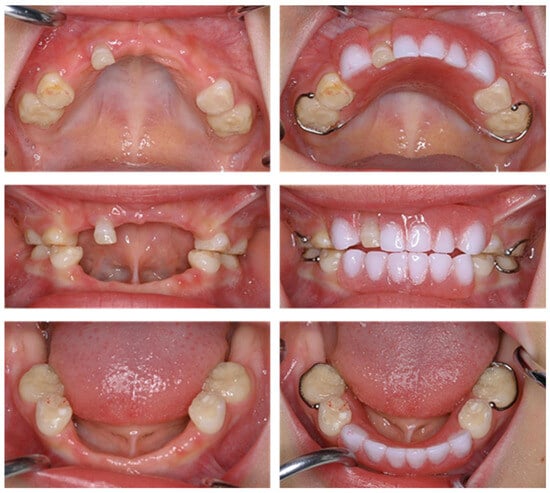

| Tooth | Time |

|---|---|

| Mandibular left primary central incisor | 1 year and 3 months |

| Mandibular right primary central incisor | 1 year and 7 months |

| Mandibular left primary lateral incisor | 2 years |

| Mandibular right primary lateral incisor | 2 years and 4 months |

| Maxillary right primary canine | 2 years and 7 months |

| Mandibular right primary canine | 2 years and 8 months |

| Maxillary right primary central incisor | 3 years |

| Maxillary left primary canine | 3 years |

| Maxillary left primary central incisor | 3 years and 9 months |

| Mandibular left primary canine | 4 years and 3 months |

| Maxillary left primary lateral incisor | 4 years and 6 months |